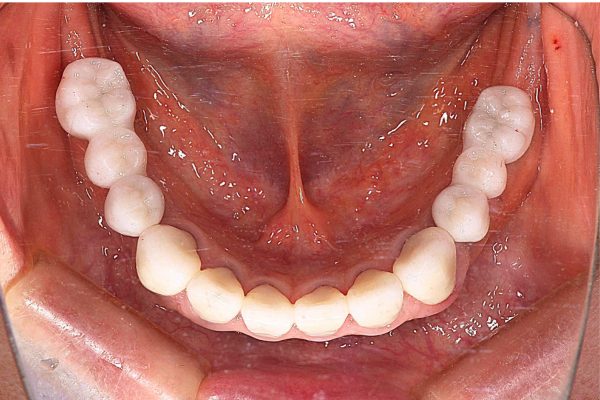

5. ジルコニア補綴による審美修復

前歯を含めた最終的な被せ物には、歯科用セラミックの中でも極めて強度と美しさを持つジルコニアを採用します。

患者さんは「白くしたい」とおっしゃったので、歯の色はA1というかなり白い色をベースにしました。

治療終了から現在で7年が経過していますが、インプラントおよび周囲の組織の状態は極めて良好です。

・治療内容: インプラント埋入(7本)、ジルコニア補綴、骨造成(GBR) ・治療期間: 約1年9か月(術後の安定確認期間含む) ・費用: 約450万円(税込) ・リスク・副作用: インプラントは外科手術を伴うため、術後に一時的な腫れ、痛み、内出血が生じる場合があります。また、喫煙の再開や毎日のセルフケアの怠慢は「インプラント周囲炎」を招き、最悪の場合インプラントが脱落する可能性があります。長期的な安定には、プロによる定期的なメンテナンスが必須です。